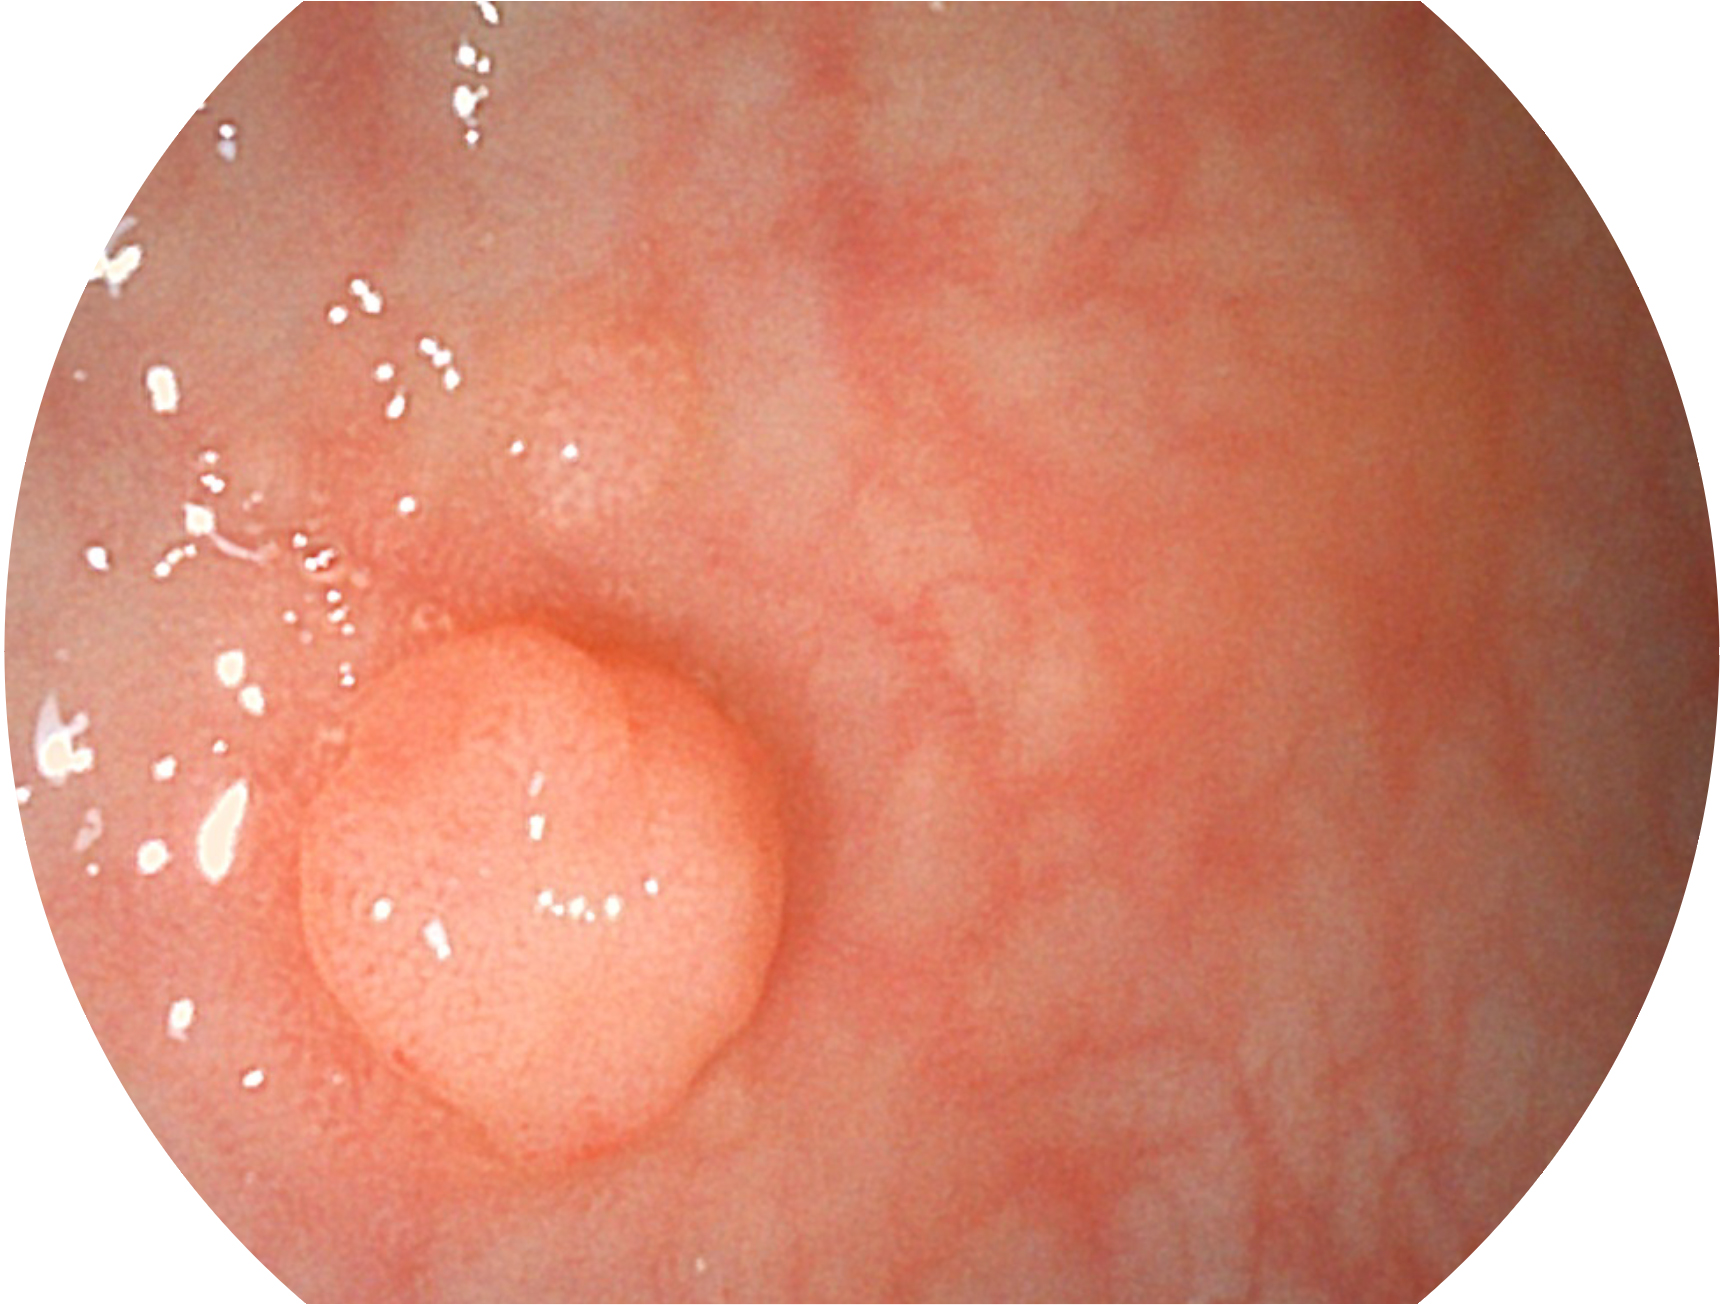

亚星官网新开发的内镜染色技术,主要是基于多波长LED 光源的开发,VLS-55Q 四波长LED 光源是由四个不同颜色的LED光按照相应照明模式所规定的特定发光比例进行合束后形成,合束后形成的照明光的光谱由红光、绿光、蓝光及蓝紫光这四个不同的波段范围构成。具有更高光谱自由度,通过光谱比例的控制,实现了聚谱成像技术,英文全称为“Spectral Focused Imaging, SFI”,缩写为“SFI”和光电复合染色成像技术,英文全称为“Versatile Intelligent Staining Technology, VIST”,缩写为“VIST”。